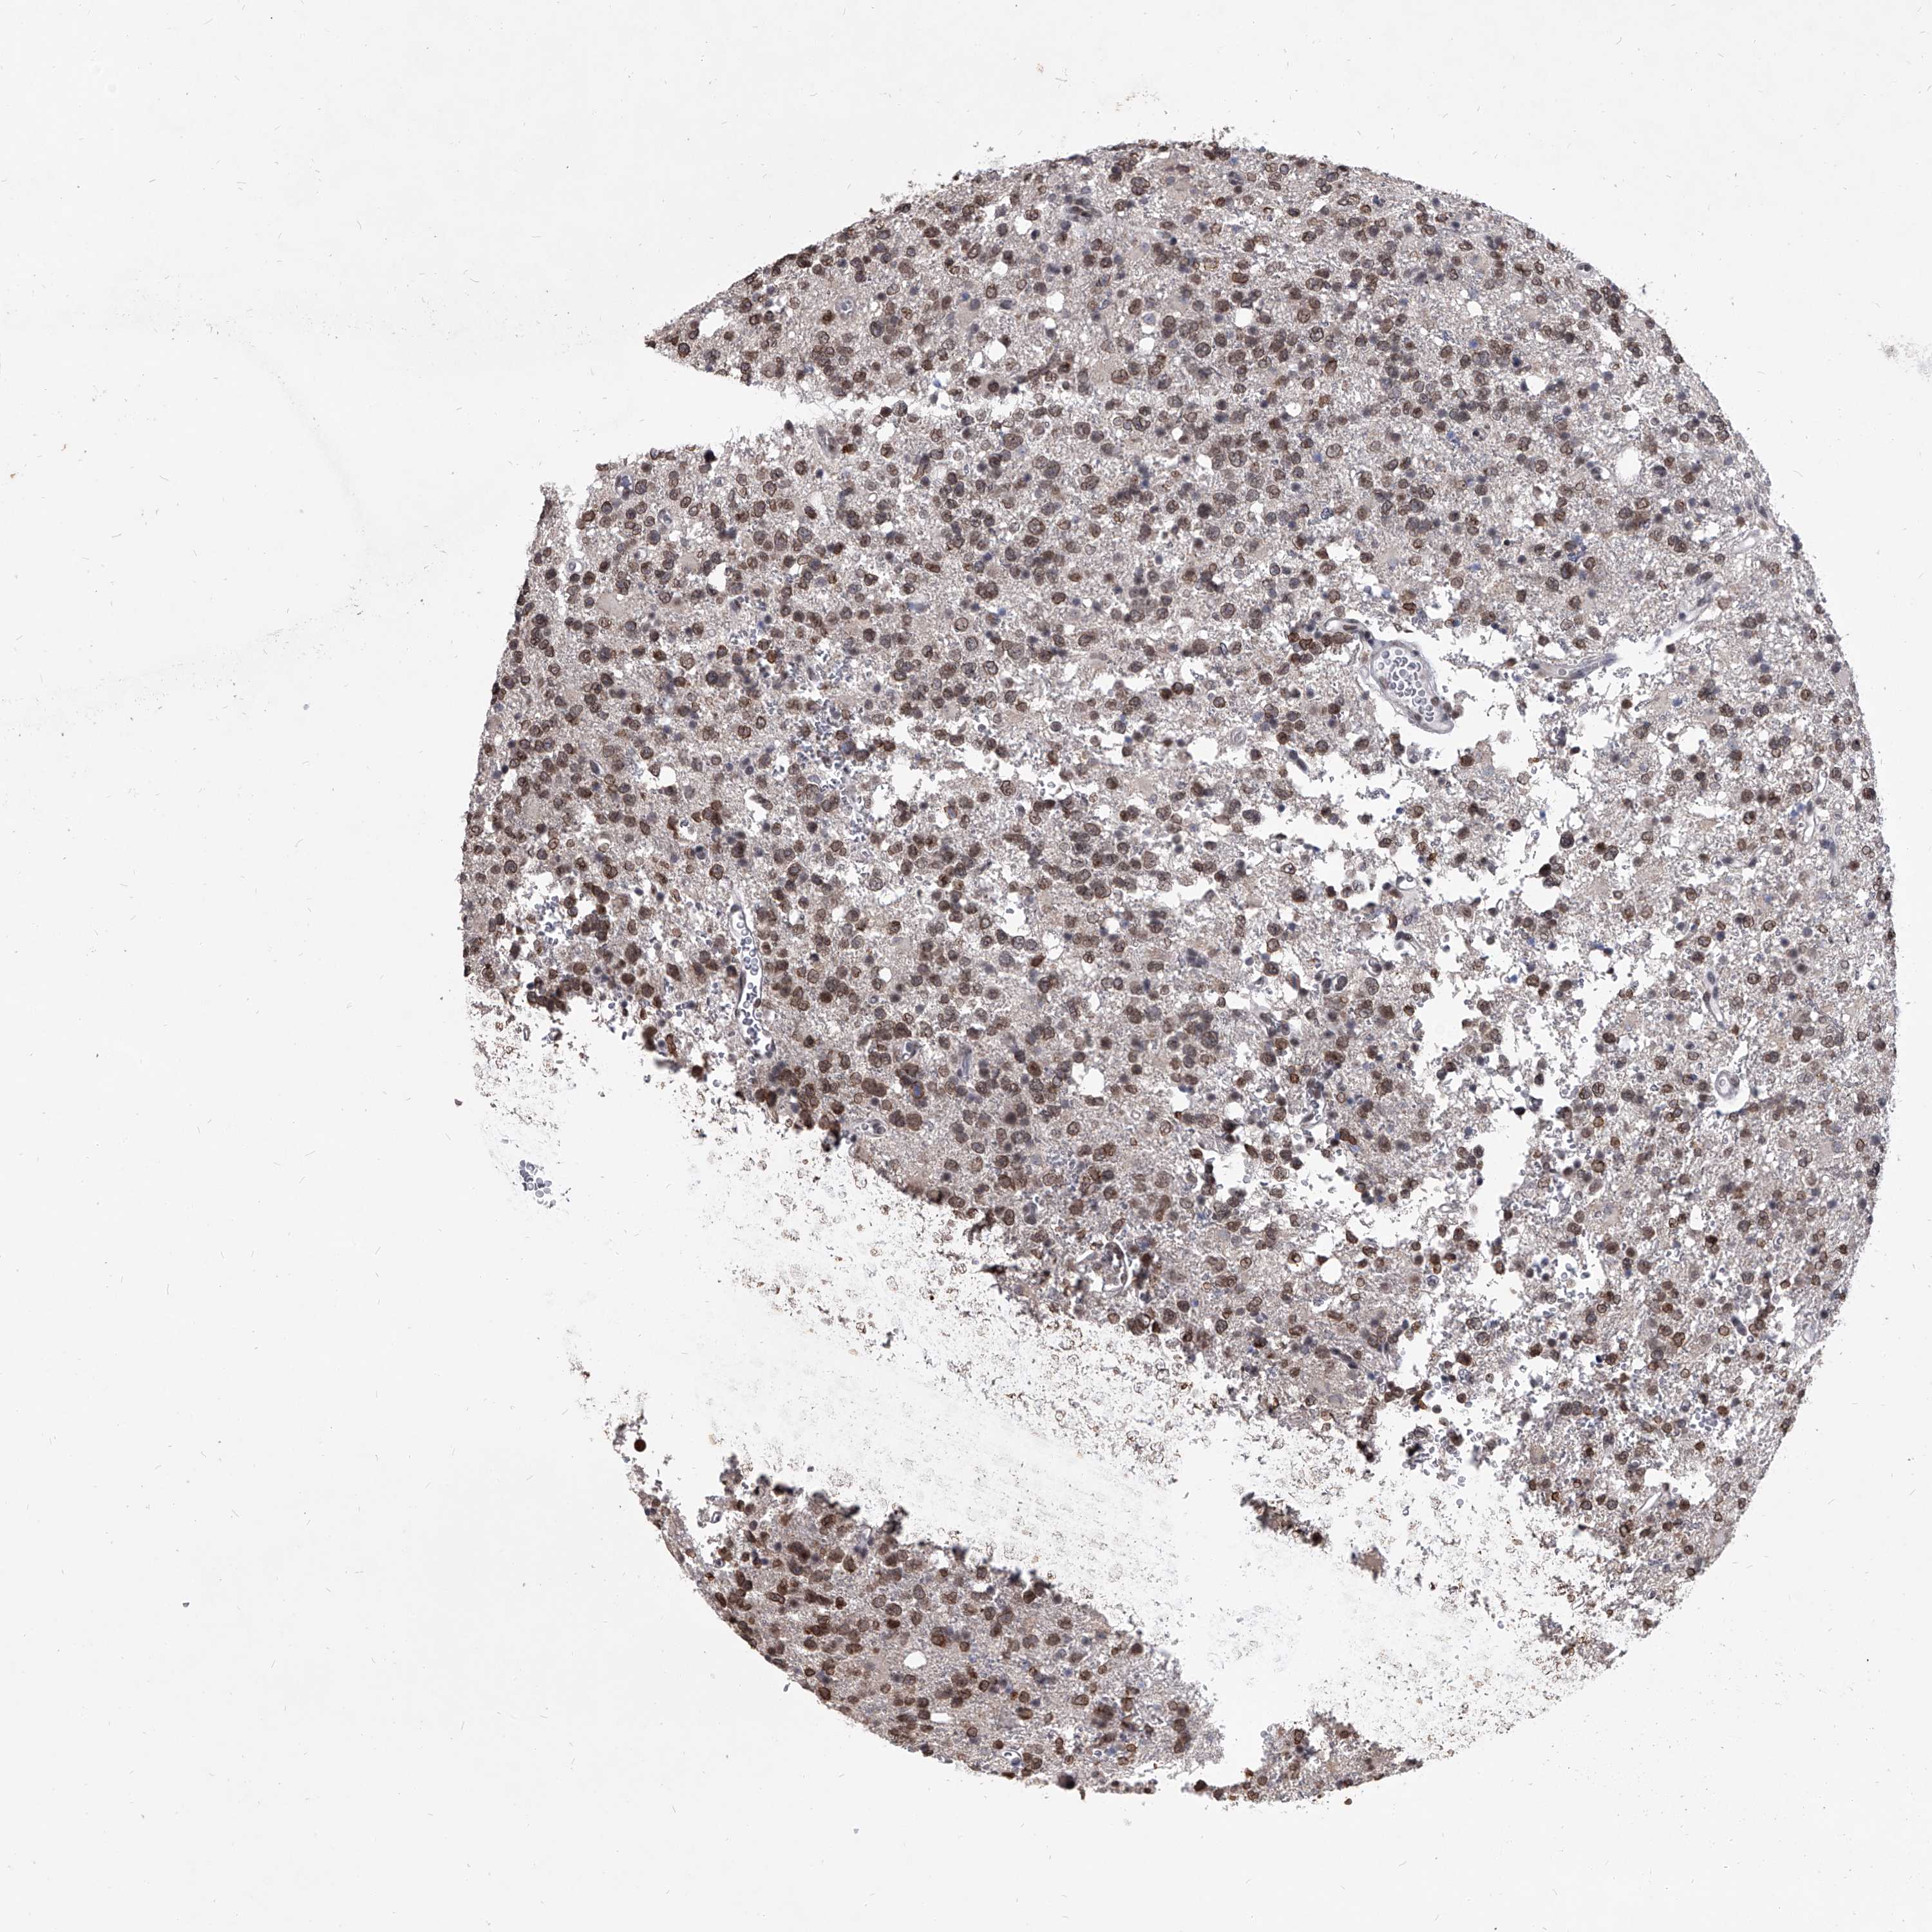

GLIOMA - Protein expressioni

A mouse-over function shows sample information and annotation data. Click on an image to view it in a full screen mode. Samples can be filtered based on level of antibody staining by selecting one or several of the following categories: high, medium, low and not detected. The assay and annotation is described here.

Note that samples used for immunohistochemistry by the Human Protein Atlas do not correspond to samples in the TCGA dataset.

Antibody stainingi

Antibody staining in the annotated cell types in the current human tissue is reported as not detected, low, medium, or high, based on conventional immunohistochemistry profiling in selected tissues. This score is based on the combination of the staining intensity and fraction of stained cells.

Each image is clickable and will lead to virtual microscopy that enables deeper exploration of all samples and also displays staining intensity scores, fraction scores and subcellular localization as well as patient and tissue information for each sample.

Antibody HPA031600

Staining

High

Medium

Low

Not detected

Intensity

Strong

Moderate

Weak

Negative

Quantity

>75%

75%-25%

<25%

None

Location

Nuclear

Cytoplasmic/membranous

Cytoplasmic/membranous,nuclear

Glioma, malignant, High grade

Glioma, malignant, Low grade

Glioblastoma, NOS